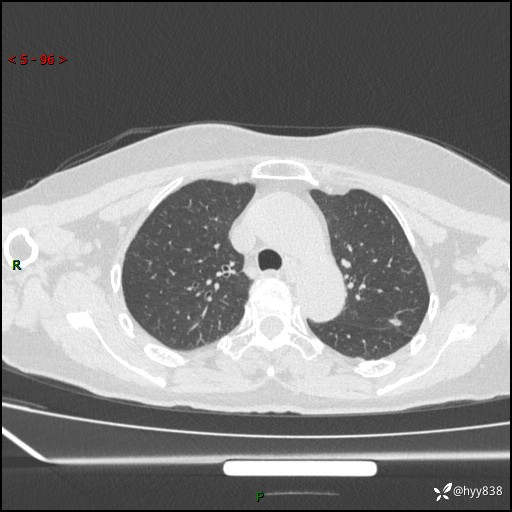

老年女性,偶然发现肺结节10天。结节不大,空洞不小,还牵拉胸膜---结果公布~

主诉:体检发现肺结节10余天

现病史:患者10余天前因“左侧鼻塞伴鼻腔异味2月”就诊于我院耳鼻喉科,查胸部CT示:左上肺结节影,建议复查。患者偶有咳嗽、咳痰,多咳白痰,无畏寒、发热,无胸痛、呼吸困难等,现为进一步明确肺结节性质,就诊于我科门诊。现以“孤立性肺结节”收住我科。 起病来,患者精神、食欲、睡眠尚可,体力、体重无明显变化。

胸部CT(2024.7.16)